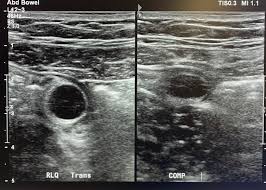

300

What is the pathology?

Appendicitis with Appendolith